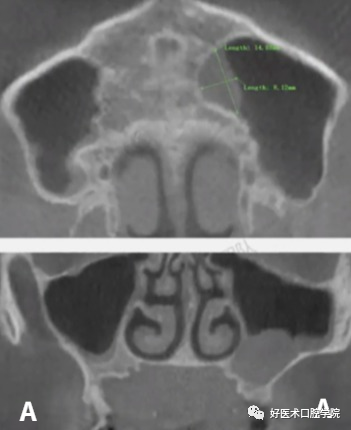

A:上颌窦粘液囊肿(周围可见骨质破坏) B:上颌窦积液(周围无骨质破坏)

上颌窦黏液囊肿多系黏液排出堵塞而使液体累积上颌窦窦口所致,囊肿内衬上皮,囊肿内充满黏蛋白,随着囊肿的增大在影像上可见病窦区密度增高,呈膨胀性扩大,多呈圆形膨隆,有时可见反应白线,囊肿周围出现骨质破坏,骨上颌窦壁轻度硬化或压迫性吸收和损伤邻近组织,患者通常会出现疼痛、肿胀、鼻塞等症状。

上颌窦粘液囊肿在我国发病率较低,据统计,仅占鼻窦粘液囊肿的3%~10%。